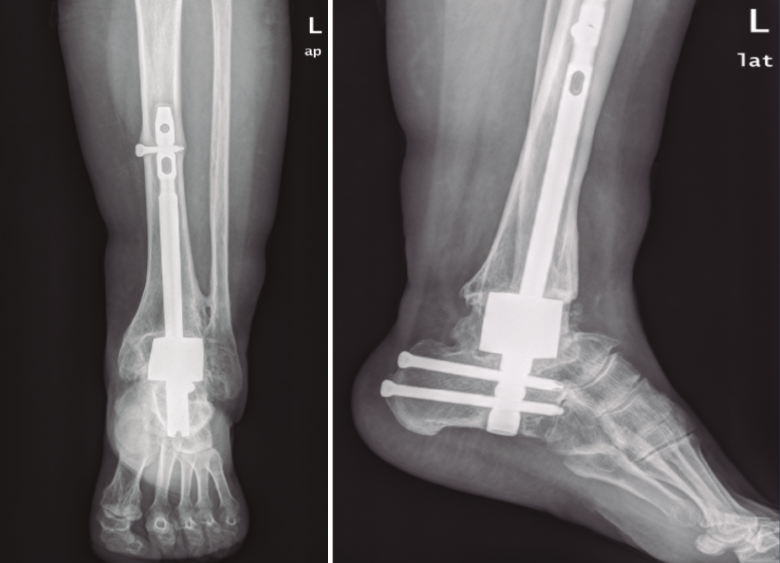

A continuación y a través del orificio central que presenta el espaciador de tantalio, se introduce bajo control radioscópico un clavo transcalcáneo de titanio, cerrojado y a compresión. La superficie anterior del mismo y los recesos laterales se rellenan con restos de hueso viable resecado y aloinjerto esponjoso. En 3 de los casos se empleó clavo VersaNail® (De Puy). En uno de los casos (el último intervenido) el clavo utilizado fue Phoenix® (Zimmer & Biomet).

En todos los casos se observaron signos de consolidación radiológica a las 24 semanas (Figuras 1 y 2). El implante de tantalio ha presentado una buena integración sin que se hayan observado signos de osteolisis o colapso en el hueso adyacente, manteniéndose invariable la longitud de la extremidad en todos los casos.

Figura 2. Radiografías postoperatorias a las 24 semanas.

El tiempo de seguimiento medio ha sido de 26 meses en los 3 primeros casos y de 7 meses en el último que se ha intervenido.